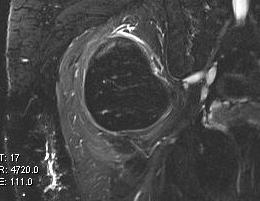

MRI

Same signal intensity as surrounding fat

Differential diagnosis liposarcoma

Large lesions

Growth

Heterogenous appearance

Deep to fascia